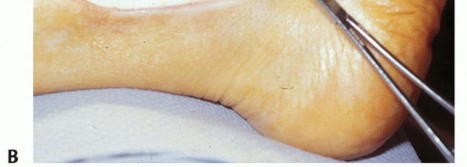

TECH FIG 1 • A. Intraoperative photograph of a left ankle (lateral approach) shows the peroneal tendons subluxing anteriorly (brevis is the gray arrowhead , longus is the white arrowhead , SPR is the black arrow). B. The peroneal tendons have been retracted anteriorly by the Penrose drain. Elevation of an anterior-based periosteal flap (outlined by dots) from the fibular groove has been completed. The black arrow shows the remnant of the SPR posteriorly. C. The tendons are relocated, after a groove-deepening procedure, into the recreated groove. The white dots outline the anteriorly based periosteal flap. It is then brought over to the posterior remnant of the SPR (black arrow). D. The flap is sutured to the remnant SPR with nonabsorbable sutures, completing the superior peroneal retinaculoplasty. |

| Suture the flap to the posterior remnant of the SPR with a series of 3-0 polybraided nonabsorbable sutures (TECH FIG 1D). | |||

| Range the ankle to evaluate the soft tissue repair, being sure that the tendons are free to move within the reconstructed peroneal tendon sheath. | |||

| Close the skin in usual fashion, and place the leg into appropriate dressings and splints with compressive bandages. | |||